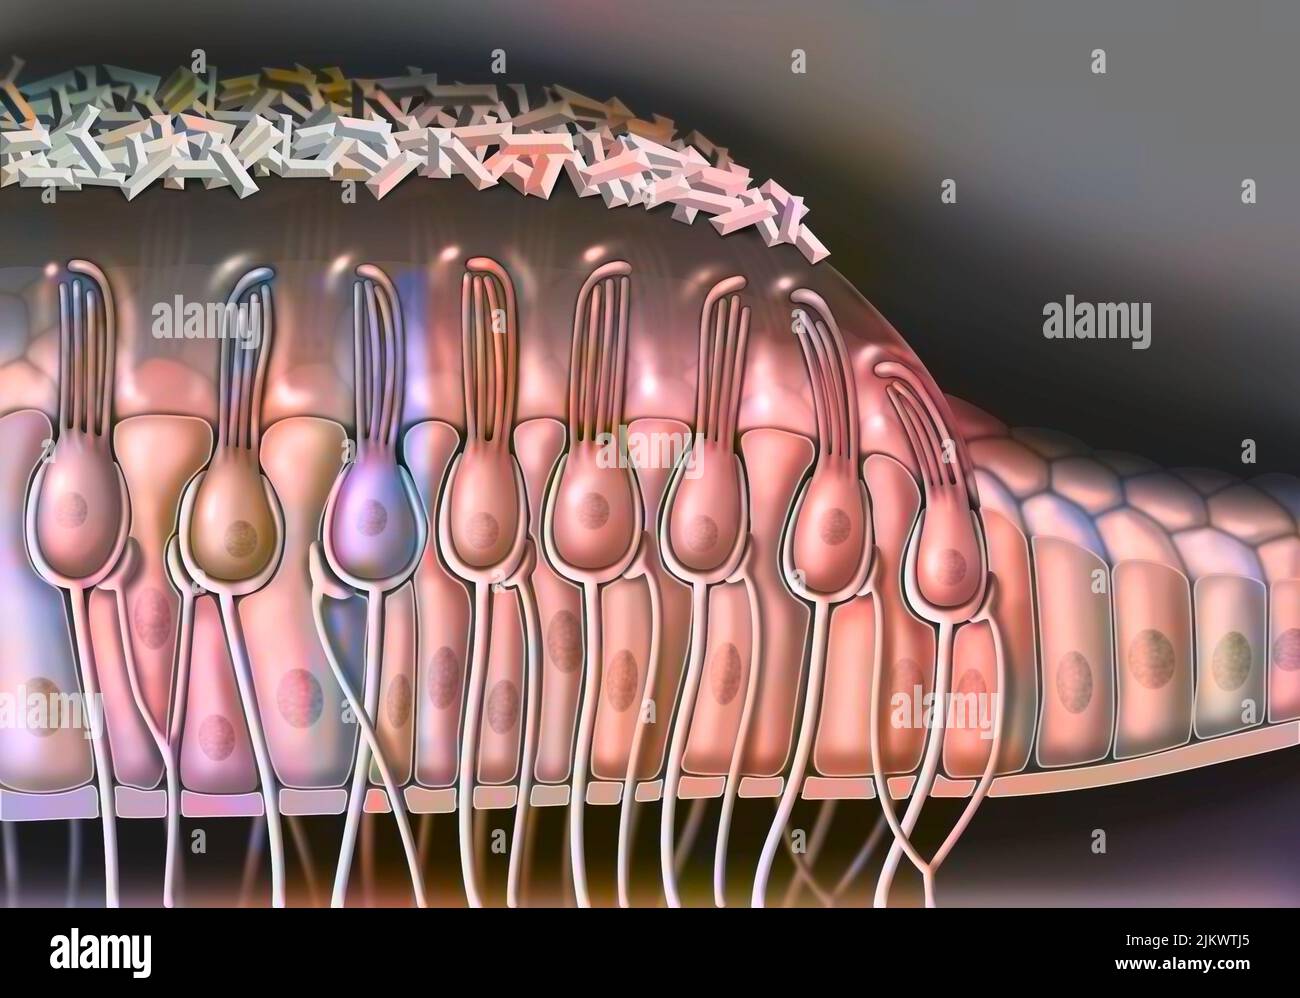

RF2JKWTKH–Canal ionique dépendant du ligand : l'attachement d'une molécule particulière provoque l'ouverture du canal.